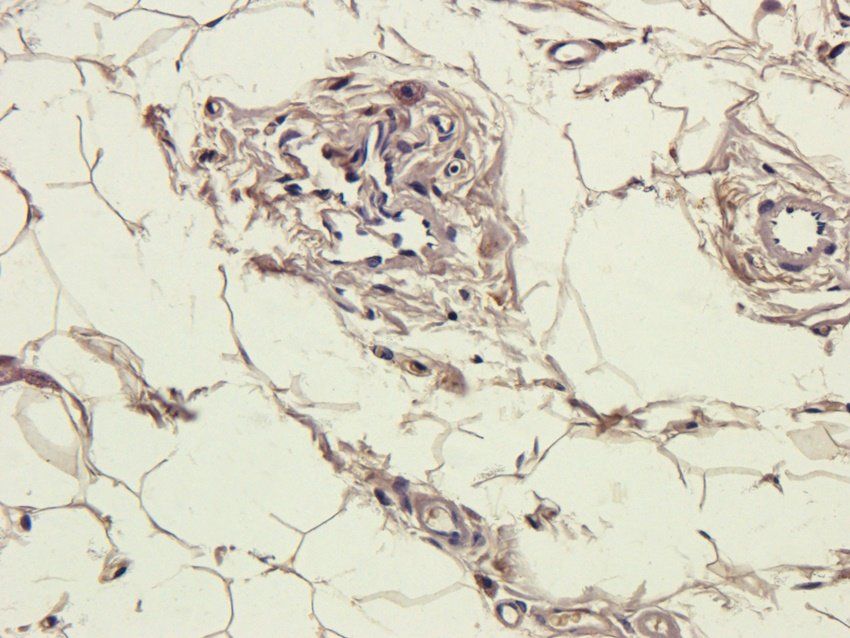

ICC, IF, IHC-P, WB

应用稀释比例:WB: 1:200-1500, IHC-P: 1:50-300, IF/ICC: 1:50-300